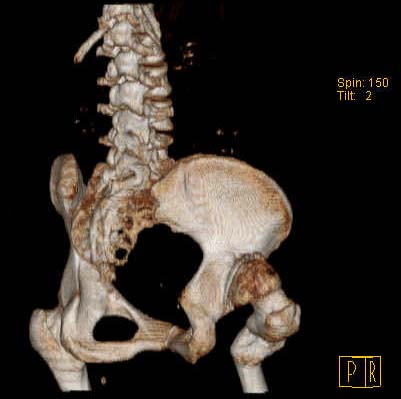

Уважаемые коллеги!Женщина, 35 летВ прошлом по поводу врожденного вывиха бедра перенесла операцию остеотомии по Шанцу

с удлинением правой ноги за счет бедра на уровне диафиза. В последнее время прогрессируют боли в правом тазобедренном суставе, порочное положение правой ноги, затруднена ходьба.Вопросы:1) Целесообразно ли эндопротезирование правого тазобедренного сустава?2) Целесообразный ли следующие действия: канал бедренной кости предполагаем вскрыть для введения ножки протеза на высоте угловой деформации, предполагаем низведение большого вертела с мышцами; протез будет подобран индивидуально, предполагается умеренная версия?В приложении рентгенограммы и трехмерная КТ.В цветном и более качественном варианте КТ размещена здесь